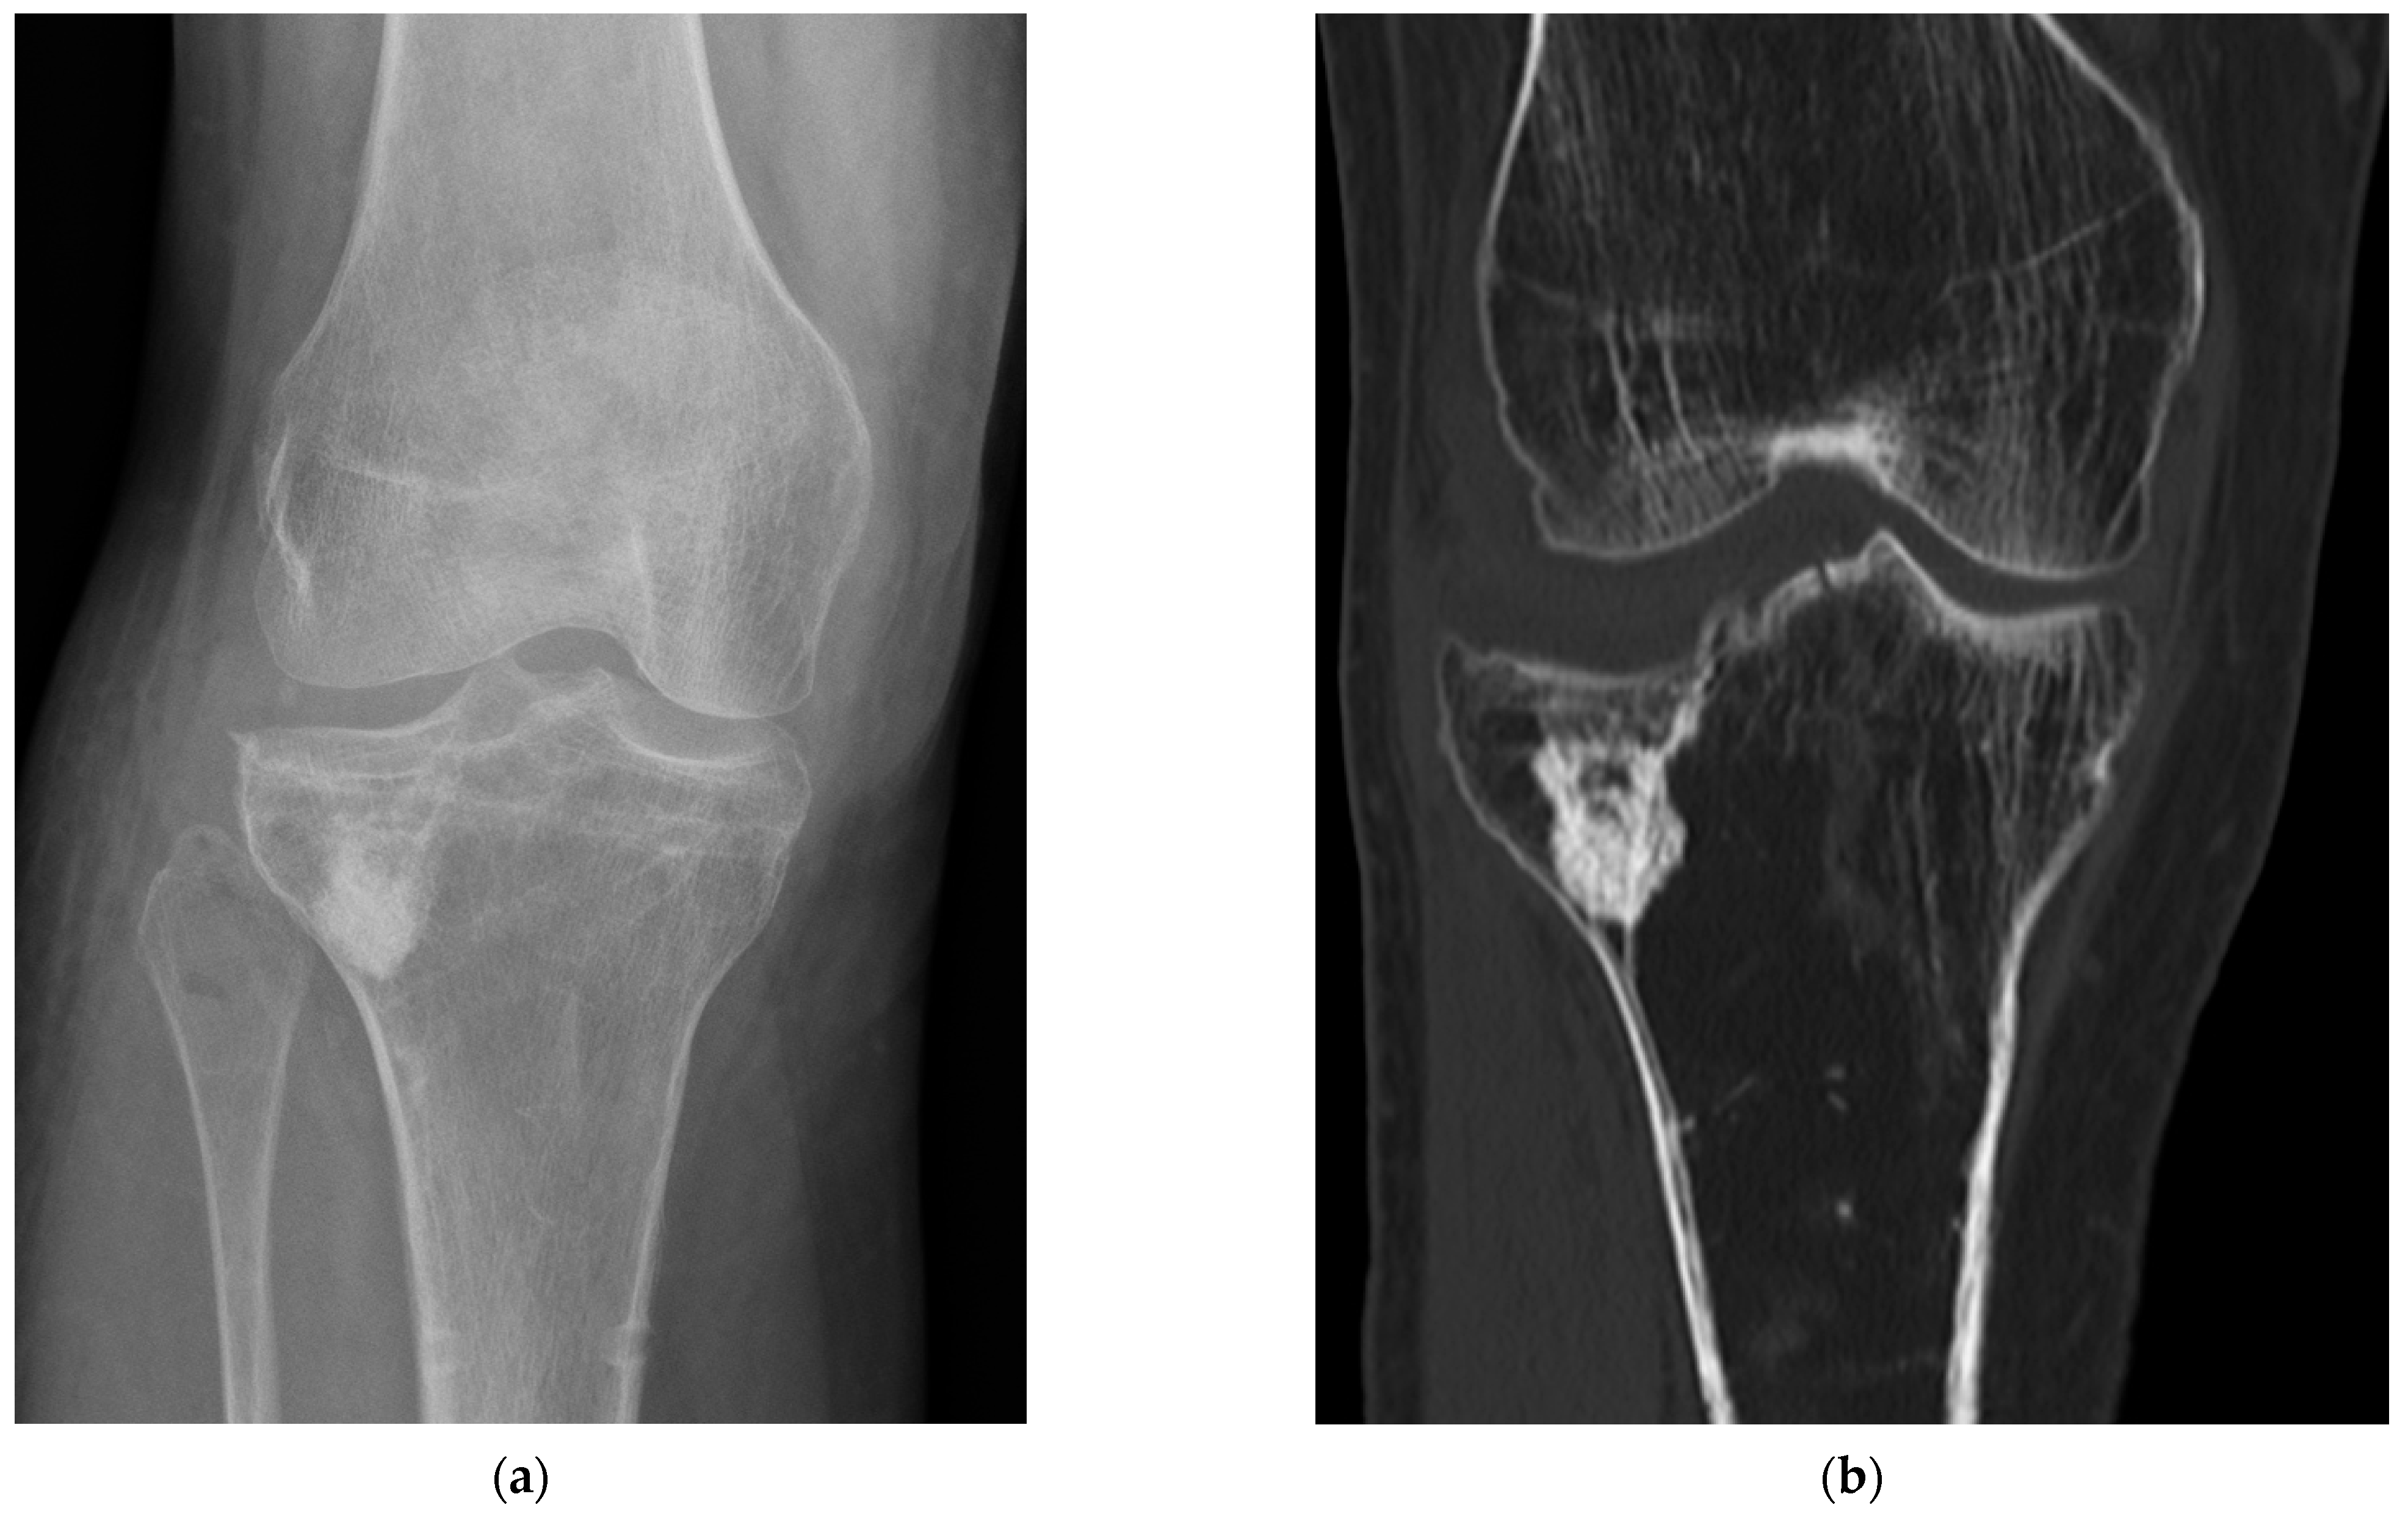

3. Discussion

4. Materials and Methods

4.4. Radiological Bone Healing Process

4.5. Postsurgical Complications